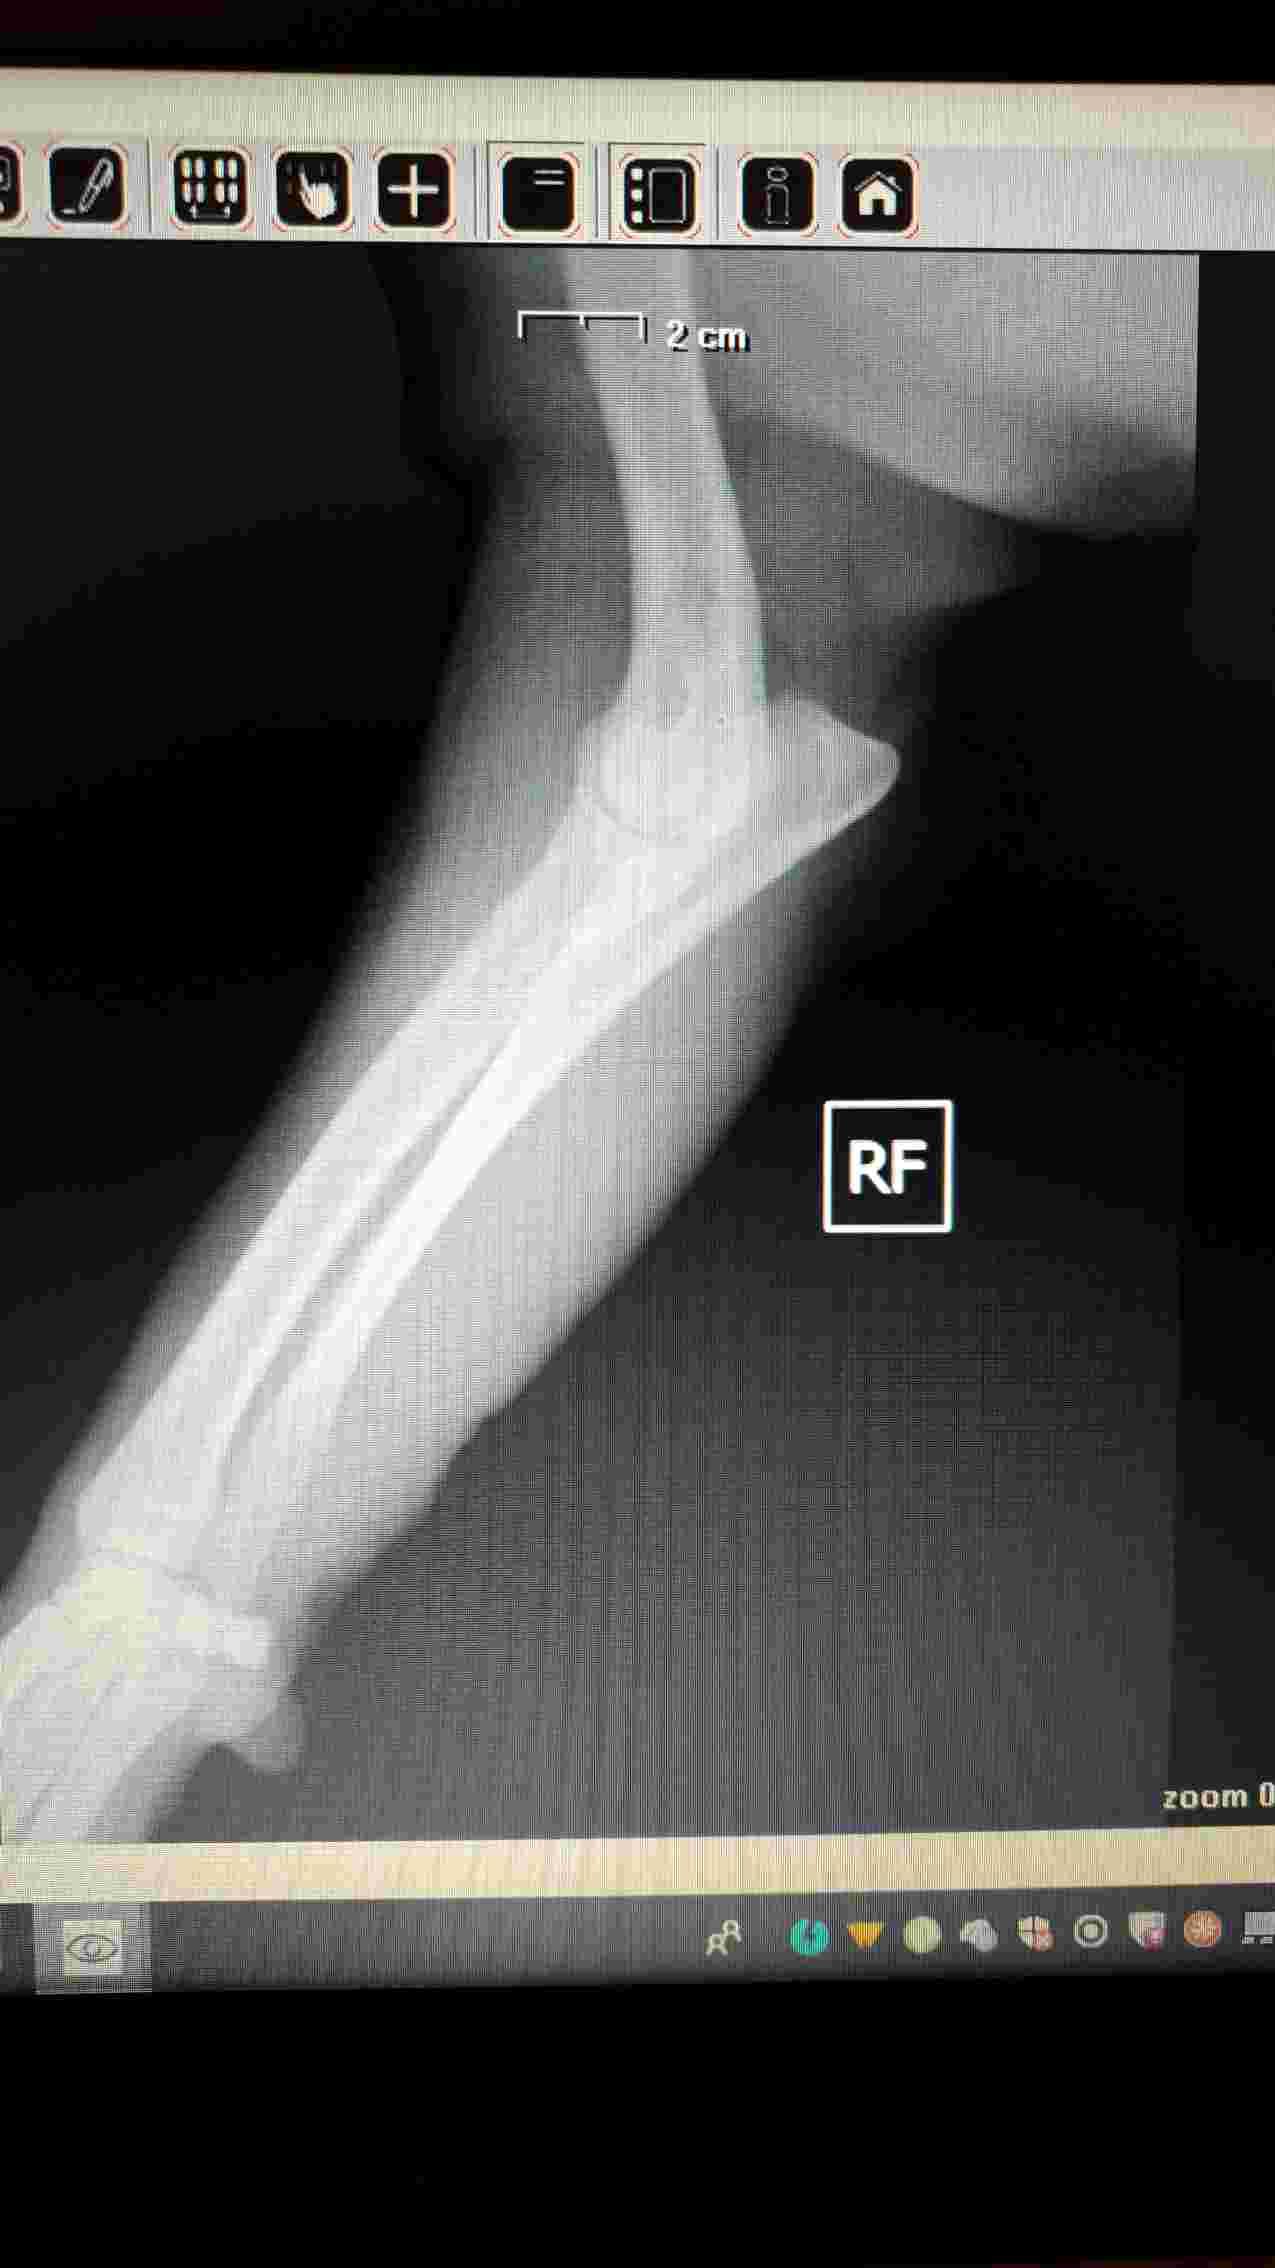

My chow chow is limping and feels some pain in right front elbow. The vet says that could be an elbow dysplasia. Any observation from you? Thank you !! P.s. He's 4 y and 7 mo old.

I do see some abnormal opacity in the elbow joint where the arrow is, so I would have to agree with your vet here. It is not possible to zoom in on x-rays that are copied here however, so its best to get a copy of the x-rays on a CD and then having them reviewed by a 2nd opinion doctor that way. Or you can ask your vet to send these to a radiologist who is well trained on picking up on small details that the untrained eye can miss. Another option is to treat medically for a minimum of 2 weeks, and if there is no improvement, then you know that is not just a muscle sprain or mild injury, and that elbow dysplasia is more likely the underlying cause. Doing a process of elimination, while still treating the pets pain, is a common thing that owners do when they are looking for a more conservative approach. If this is indeed elbow dysplasia, then I would recommend a referral to an orthopedic specialist if you want to pursue treatment. Treatment for this condition is often surgery. Poor guy. I hope that you can get him some relief soon. Best wishes and take care!